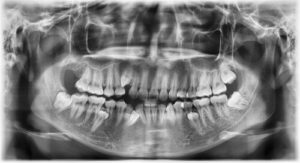

After wisdom tooth removal, particularly if your upper wisdom teeth were extracted, the proximity of your sinuses becomes a factor. In some cases, the roots of the upper wisdom teeth are close to, or even touching, the sinus cavities. A small communication between the sinus and the mouth, called an oroantral communication, can occur during removal.

Blowing your nose creates pressure in your nasal and sinus passages. If a connection exists between the sinus and the extraction site, this pressure could cause air to pass into the wound, potentially leading to delayed healing or complications like infection.